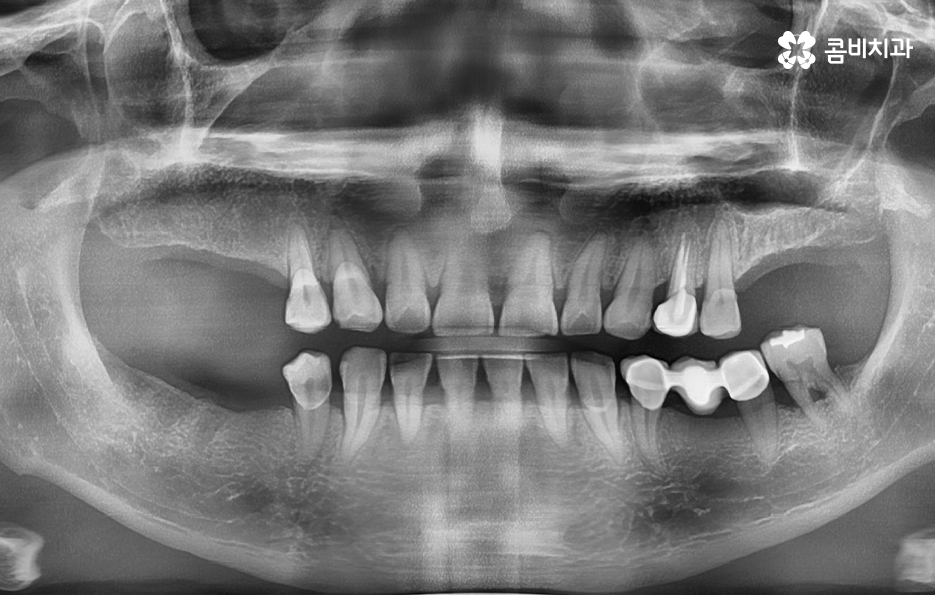

출처 아카이브 열기사고로 인해 치아를 잃게 되는 경우가 아니라면 일반적으로 치아는 노년에 이르러 상실하게 된다는 인식이 있지만 30,40대 뿐아니라 빠른 경우에는 20대에도 임플란트를 하시는 분들도 종종 볼 수 있는데요

치아 건강은 타고난 치아의 튼튼함도 수명에 어느 정도 영향을 주겠지만 나이가 들수록 후천적인 관리의 중요성이 더 높다고 할 수 있어요. 40대만 해도 아직 젊은 나이임에도 불구하고 40대 이전에 치아를 잃게 되는 보편적인 사례를 살펴보면 어릴 때 치과에 대한 안 좋은 기억으로 인하여 치과 검진을 잘 받지 않고 참을 만큼 참다가 뒤늦게 치과에 방문하여 치아를 발치까지 하게 되는 사례를 자주 볼 수 있어요

특히 30대 이후에는 충치 외에도 치주염이 점점 심해져서 치아를 발치하게 되는 사례가 많기 때문에 임플란트 치료 과정에서 뼈이식을 함께 고려해야 하는 경우도 있는데요. 오늘은 40대임플란트 이제 알아보시는 분들을 위해 40대 이기 때문에 좀더 고민해야 하는 점들과 치료 과정, 주의사항에 대해 알아볼 거예요

40대임플란트 치료에 대해 알아보신다면 우선 치아를 상실한 원인에 따라서 치료 방법이 다소 차이가 날 수 있는데요. 대표적으로 충치가 심해져서 발치를 하게 된 사례와 치주염으로 인해 잇몸이 약해져서 발치하게 된 사례로 구분해 본다면 충치 만으로 치아를 발치한 경우 잇몸 상태가 양호할 때 원데이임플란트로도 치료가 진행되거나 무난하게는 일반적인 임플란트 치료 과정으로 진행될 수 있어요

반면에 치주염이 심해져서 치조골이 녹아내리고 이미 치아의 뿌리가 보일 정도로 잇몸이 약해진 상태에는 치아 발치 후 잇몸이 충분히 회복한 뒤 임플란트를 식립할 수 있는 잇몸 뼈가 충분한지 확인 후 경우에 따라서는 뼈이식이 추가될 수 있는데요.

생각보다 많은 40대 환자분들이 충치 외에도 치주염으로 인해 풍치 진단을 받고 치아를 발치하게 되는 사례가 많기 때문에 40대임플란트 치료 과정 중에 잇몸 뼈의 중요성에 대해 설명드려야만 왜 나는 치료 방법이 달라지고 뼈이식을 받아야 하는지 등과 같은 궁금증을 해소할 수 있을 거예요

하지만 앞서 설명드린 것처럼 30대 이후에는 치주질환을 앓게 되는 분들이 급격히 늘어나며 치주질환 관리가 잘 안되신 분들의 경우 40대에도 치주염으로 인해 치아를 상당수 잃게 되는 사례도 적지 않게 확인되고 있어요